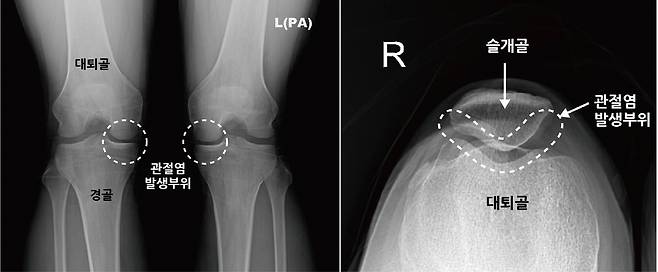

퇴행성 무릎관절염이라고 하면 보통 무릎 위아래 사이의 관절 손상을 생각하기 쉽지만 무릎 앞쪽의 슬개대퇴관절염도 무릎 관절염의 주요 원인이다. 이 질환을 방치할 경우 말기 퇴행성무릎관절염으로 진행될 수 있기 때문에 주의를 요한다.

슬개대퇴관절염은 슬개골(무릎 앞에 있는 삼각형의 뼈)과 대퇴골 사이 연골에 손상이 발생하거나 선천적으로 슬개골이 대퇴골에 제대로 맞자 않아 무릎이 움직일 때 슬개골이 어긋나면서 연골에 스트레스가 가해져 발생한다.

우리가 일반적으로 알고 있는 무릎 관절염(퇴행성 관절염)은 대퇴골과 경골 사이에 있는 연골 손상으로 관절염이 진행될수록 무릎의 관절간격이 좁아지기 때문에 심한 경우, X-ray만으로도 비교적 쉽게 진단이 가능하지만 슬개대퇴관절염의 경우 질환이 어느정도 진행된 경우에도 X-ray 검사상 이상 소견을 발견하기 어렵기 때문에 진단이 쉽지 않다. 그래서 종종 진단과 치료 시기를 놓치게되어 증상이 악화되기도 한다.